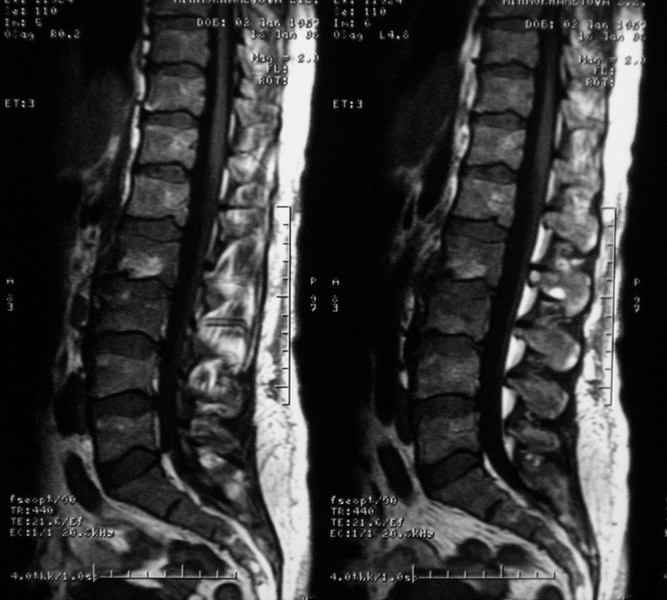

MRI через три недели

|

По данным представленных КТ и МРТ у больной имеется достаточно выраженная степень деструкции тел позвонков (около 30% общей костной массы тела позвонка), что определяет высокий риск возникновения патогических переломов и появления локальной кифотической деформации на этом уровне.

Уважаемый доктор! судя по последнему МРТ процесс затрагивает соседние позвонки с переходом процесса через диск. Для туберкулёза как раз и характерна картинка "целующихся" позвонков. При бактериальном процессе диск страдает лишь вторично. Туберкулиновые пробы могут быть в пределах нормы, лёгкие - чистые. Вообще туберкулёз последнее время стал очень коварен и атипичен. Такие случаи отмечались у детей старшего возраста.

Данные МРТ выкладываешь некорректно - это не "контроль в динамике", а поход по Сусанинским местам, сравниваемые срезы за разные даты должны быть одинаковыми.